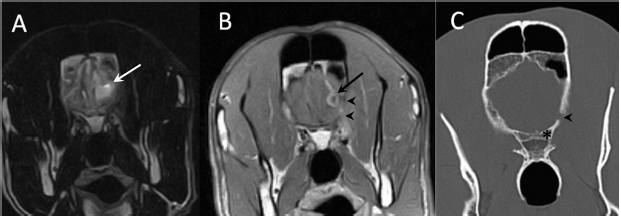

A 3-year-old female Great Dane was referred for acute onset behavioral changes (aggression and disorientation) of 2 weeks duration, and seizures from 24 hours prior to presentation. Physical examination revealed no abnormalities in body temperature, body condition score, heart rate, pulse quality, or cardiopulmonary auscultation. All lymph nodes were considered of normal size and no pain was elicited upon manipulation of the orbital, aural, or cranial musculature. Neither was there any history of dermatological or traumatic lesions in the eye, ear, or mouth. The neurological examination revealed the patient to be obtunded with decreased postural reactions and menace response worse in the left side. Neuroanatomic lesion localization was considered focal in the right prosencephalon with a possible increase in intracranial pressure. Hematological and serum biochemical analysis showed no abnormalities. Magnetic resonance imaging was performed using a low-field magnet (Airis Mate; Hitachi, Tokio, Japan). The study revealed a left-sided single frontal intra-axial lesion affecting gray and white matter adjacent to the internal capsule at the level of the optic canal (Fig. 1). The lesion presented signal homogeneity characterized by hyperintensity on T2W and FLAIR sequences and hypointensity in T1W sequences with peripheral enhancement after intravenous contrast administration (Fig. 1A and 1B). The lesion had a round shape with the greatest diameter of 2.84 cm. This enhancement was also recognized in the surrounding meninges following the brain surface following sulci. A small linear tract observed was directed dorsally from the lesion through the corona radiata (Fig. 1B). The lesion was associated with extensive perilesional vasogenic edema that worsened the mass effect characterized by a midline shift. The orbital and medial pterygoid muscles also showed an intense enhancement (Fig. 2). The wing of the presphenoid bone was thinner than the contralateral bone (Fig. 1B). A CT scan (Astelion 16, Toshiba, Tokio, Japan) was performed after MRI that allowed the identification of osteolysis in the presphenoid bone immediately dorsal to the orbital fissure (Fig. 1C). CT scan also revealed a hypoattenuating intra-axial lesion located in the left frontoparietal lobe together with diffuse hypoattenuation of tissues adjacent to the left optic nerve and the left pterygoid muscle. Finally, CSF analysis showed no abnormalities. On the basis of advanced radiological findings, the main differential diagnosis was an intracranial abscess due to the extension of the extracranial septic process through presphenoid bone. Because of rapid neurologic deterioration and suspected increased intracranial pressure, surgical excision was planned. A modified left rostrotentorial craniectomy was performed. Temporalis muscle and fascia were retracted, extending the incision cranially through the temporal line. Once the frontal and presphenoid bones were exposed an area of osteolysis was observed in the wing of the presphenoid bone immediately dorsal to the orbital fissure. The craniectomy (approximately 3 cm diameter) was centered on the osseous defect. A mucopurulent discharge presented immediately after the incision of the dura mater. A sample was collected for its microbiological study. The surgical site was flushed with sterile saline revealing the tip of a grass awn which was extracted from the brain parenchyma together with a small amount of purulent fluid (Fig. 3). After extensive flushing, the meninges were left open to allow drainage and the incision was closed as per routinely. Postoperative CT showed the correct location of the craniectomy and resolution of the abscess which was substituted by gaseous content but remained inside and on the dorsal surface of the frontal lobe (Fig. 4). Immediate postoperative therapy consisted of amoxicillin + clavulanic acid (Synulox 500, Zoetis Spain SL) 22 mg/kg PO, q8h; marbofloxacin (Marbocyl P80, Vetoquinol SA) 5 mg/kg PO, q24h; metronidazole (Flagyl 250, Sanofi-aventis SA) 15 mg/kg PO, q12h; prednisone (Prednisona Kern Pharma 30mg, Kern Pharma) 0.5 mg/kg PO, q12h; tramadol (Tramadol retard Combix 100 mg, Laboratorios Combix S.L.U) 2 mg/kg PO, q8h; famotidine (Famotidina Normon 40 mg; Laboratorios Normon SA) 0.7 mg/kg PO, q24h; and phenobarbital (Phenoleptil 100 mg, Le Vet BV) 2.5 mg/kg PO, q12h. Cultured samples were positive for Pseudomonas aeruginosa sensitive to ciprofloxacin, imipenem, and amikacin among other antibiotics. Based on these results, antibiotic therapy was changed to ciprofloxacin (Ciprofloxacino 500, Laboratorios Normon SA) 10 mg/kg PO, q12h and metronidazole 15 mg/kg PO, q12h for 2 months. Prednisone, tramadol, and famotidine were withdrawn and phenobarbital was maintained at 2.5 mg/kg q12h. Six-month post-operative revision magnetic resonance revealed no signs suggesting the existence of an inflammatory process (Fig. 5). In the area where the abscess had been located, a fluid-filled cavity suggesting being CSF was observed. One year follow-up revealed the patient had seizures every 3 months with neurological examination remaining normal. The patient died 2 years later of unrelated causes.

Fig. 1. (A) Transverse T2-weighted image, (B) transverse post-contrast T1-weighted image, and (C) transverse CT image obtained at the level of the optic canal (asterisk). The lesion can be seen as a hyperintense (arrow in A) and ring-enhancing mass (arrow in B) located in the left frontal lobe. Note thinning of the wing of the presphenoid bone (arrowheads in B and C).